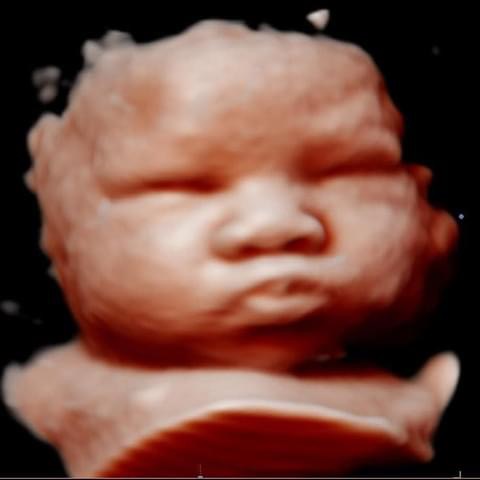

All photos are from our equipment and are of our actual clients.